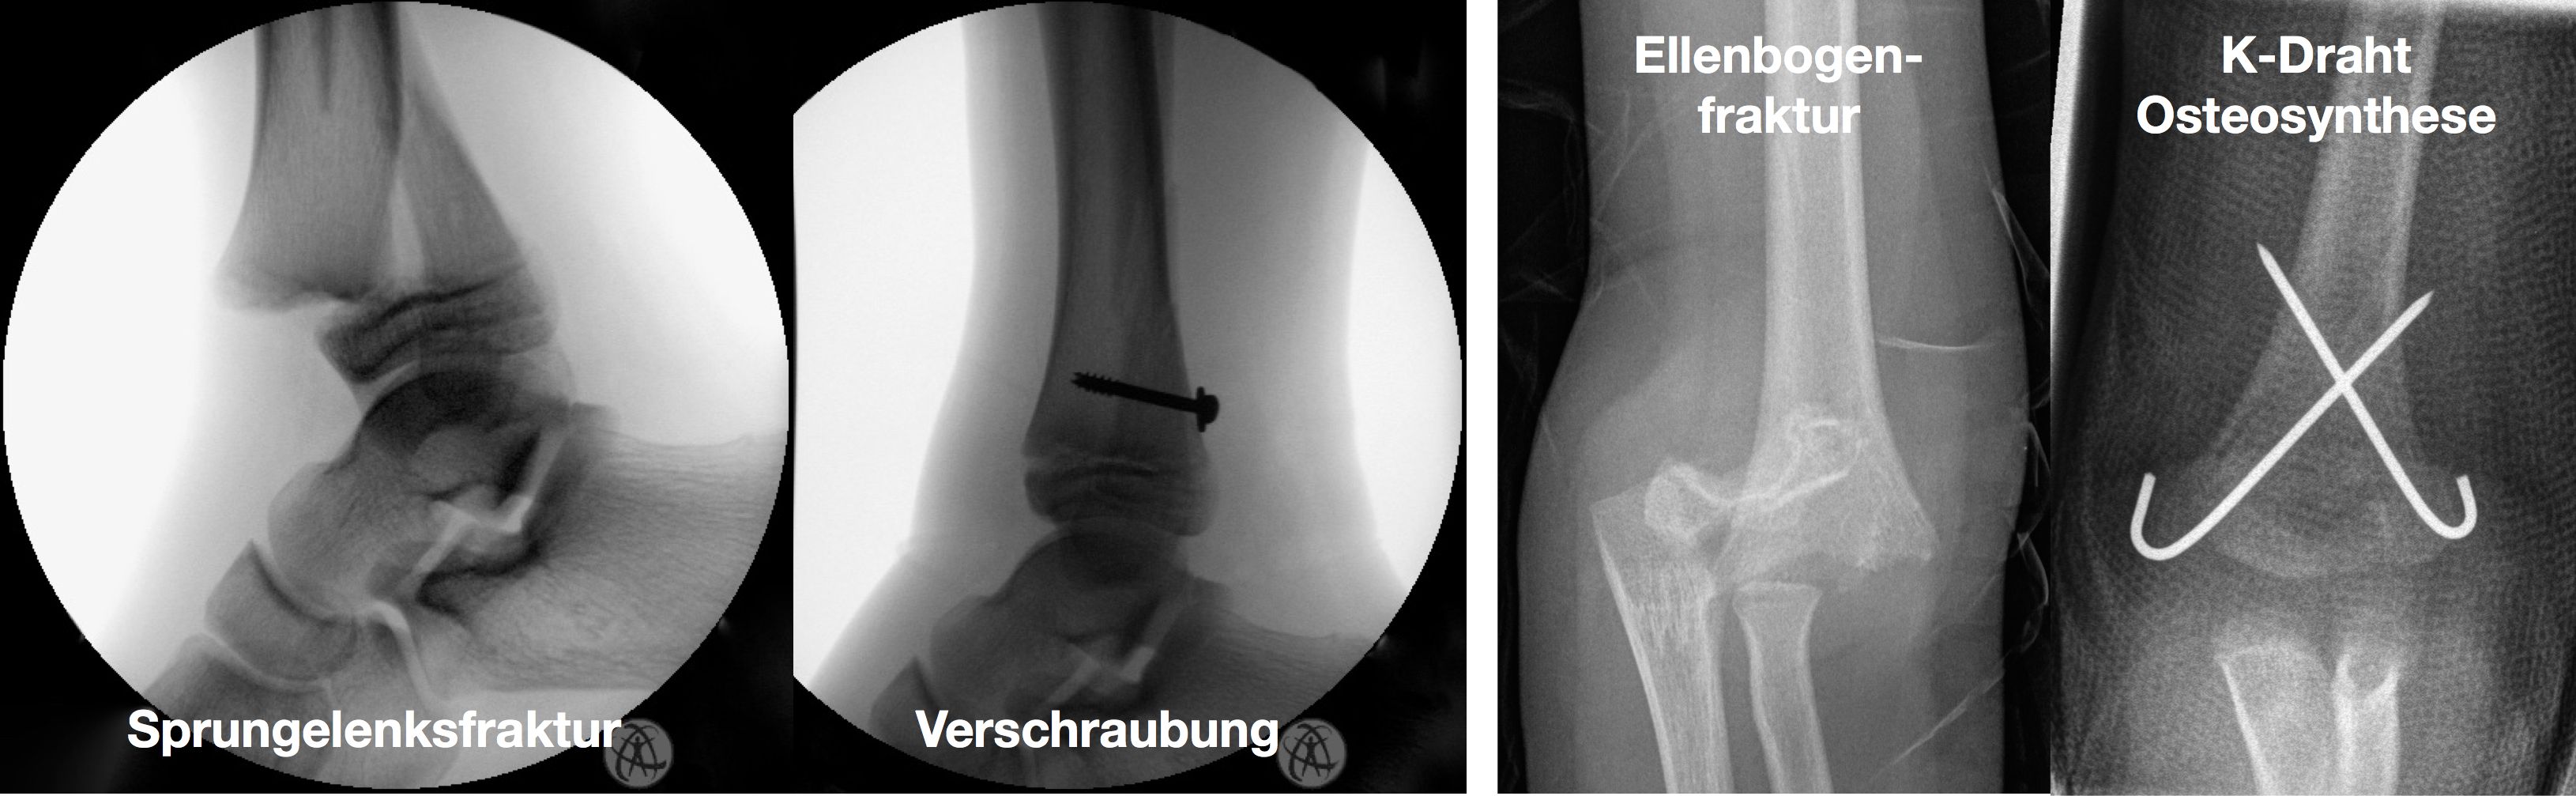

Kirschner-Draht-Osteosynthese

Andere Verfahren der operativen Frakturversorgung im Kindesalter sind die Kirschner-Draht-Osteosynthese, die Verschraubung, der Fixateur und die Plattenosteosynthese. Metallentfernungen werden ambulant durchgeführt, Nachuntersuchungen zum Ausschluss etwaiger Wachstumsstörungen erfolgen in unserer Frakturensprechstunde.

Einige Frakturen müssen auf Grund ihrer Achsabweichung operiert werden. In einer Narkose wird die Fraktur eingerichtet und ggf. mit Metall stabilisiert. Dazu stehen eine Reihe von Methoden (Osteosynthesen) zur Verfügung, die speziell für Kinder entwickelt wurden, um Wachstumsfugen zu schonen und nicht zu verletzen: Die ESIN (elastisch stabile intramedulläre Nagelung) hat sich als minimal invasives Standardverfahren zur Stabilisierung von Schaftfrakturen der großen Röhrenknochen (Unterarm, Oberarm, Unterschenkel, Oberschenkel) etabliert. Die Implantate können über winzige Schnitte eingebracht werden, eine gipsfreie Nachbehandlung ist ein weiterer entscheidender Vorteil.